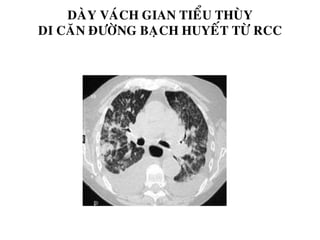

DAØY VAÙCH GIAN TIEÅU THUØY

DI CAÊN ÑÖÔØNG BAÏCH HUYEÁT TÖØ RCC